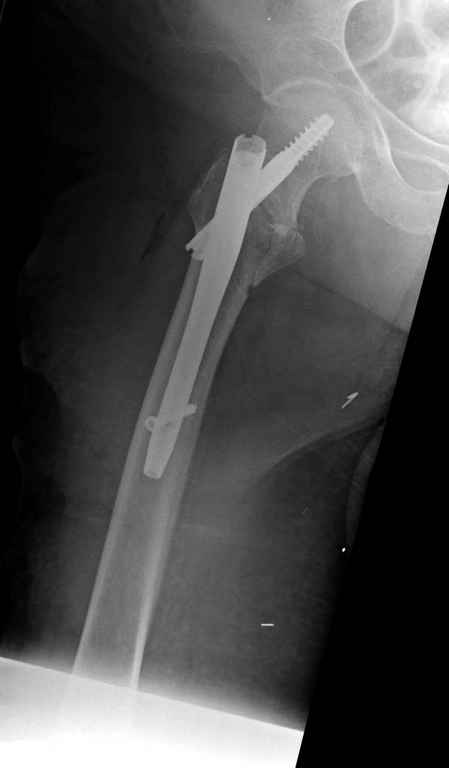

В данном случае в головке бедра и в вертлужной впадине огромный дефект, навряд ли удалением импланта или заменой на другой можно сохранить сустав.

Вашему вниманию представляется похожий случай, пациентке 70, осложнился в течение одного месяца после операции. Ревизия с заменой сустава, кабельная фиксация на трохантер. При установке в дистальном диафизе обнаружен тонкий кортикальный слой и сделана профилактика от возможного перелома аллографтом.